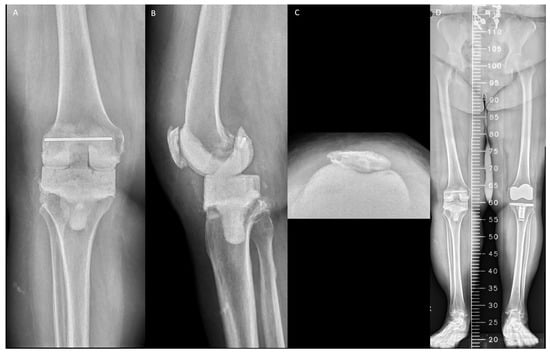

Spacer malalignment was defined as medial distal femoral angle <2° or >8° of valgus [18] (Figure 2A), medial proximal tibial angle (PTA) <−3° or >3° deviation from neutral [19] (Figure 2B), posterior tibial slope angle <0° or >7° of flexion [20] (Figure 2C), flexion contracture >15° of flexion [21] (Figure 2D), and recurvatum deformity >5° of extension [22] (Figure 2E); spacer malposition such as anterior femoral notching >3 mm in depth [23] (Figure 2F), and mediolateral or anteroposterior overhang of tibial spacers >3 mm [24] (Figure 2G,H). Cementing technique of spacers with or without cement stem extension was also recorded (Figure 2I,J). All the above data were measured on anteroposterior and lateral short-leg radiographs obtained 1 week after RA [25]. Lower-limb malalignment was defined as a hip–knee–ankle angle <−10° (severe varus) or >10° (severe valgus) on a scanogram [26] (Figure 2K). Patellar maltracking was defined as a lateral patellar tilt >10° on the Merchant view [27] (Figure 2L). Data were measured separately by the same three physicians, and the mean value was calculated. Mixed outliers were also recorded for each patient.

Figure 2. Malalignment and malposition of articulating spacer: (A) medial distal femoral angle, 100°; (B) medial proximal tibial angle, 83°; (C) posterior tibial slope angle, 96°; (D) flexion contracture, 26°; (E) recurvatum deformity, 11°; (F) femoral spacer notching (arrowhead); (G) medial overhang of tibial spacer (arrowhead); (H) anterior overhang of tibial spacer (arrowhead); (I) femoral spacer without cement stem extension (arrowhead); (J) tibial spacer without cement stem extension (arrowhead); (K) severe varus deformity with hip–knee–ankle angle, 16°; and (L) maltracking with lateral patellar tilt, 14°.